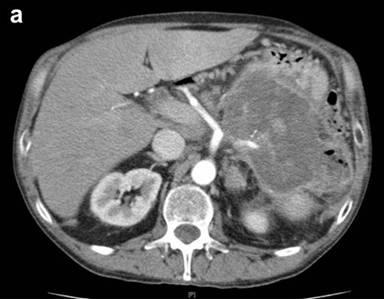

A 64-year-old man, with past medical history of high blood pressure and type 2 diabetes was evaluated in our outpatient clinic due to anemia. He also complained about mild dyspepsia and low-back pain over the last 18 months. Conventional blood tests showed microcytic anemia. Tumor markers were normal, except for CA 19-9 203 U/mL (reference range: 0-39 U/mL). A contrast-enhanced computed tomography (CT) scan of the abdomen showed a 12x7 cm inhomogeneous, low-density mass originating from the body and tail of the pancreas. The mass invaded the posterior gastric wall, the splenic flexure of the colon and the spleen. The superior mesenteric artery and the celiac axis were not involved; however, the splenic artery was amputated at its origin (Figure 1a). The Wirsung duct at the pancreatic head was enlarged (Figure 1b), with splenic vein thrombosis, segmental portal hypertension and esophageal varices.

Figure 1. Preoperative contrast-enhanced CT-scan at the celiac axis level. a. A large low-density mass in the pancreatic body and tail infiltrating the posterior gastric wall, the splenic flexure of the colon and the spleen. The amputation of the splenic artery is evident. b. Dilated main pancreatic duct (white arrow). |